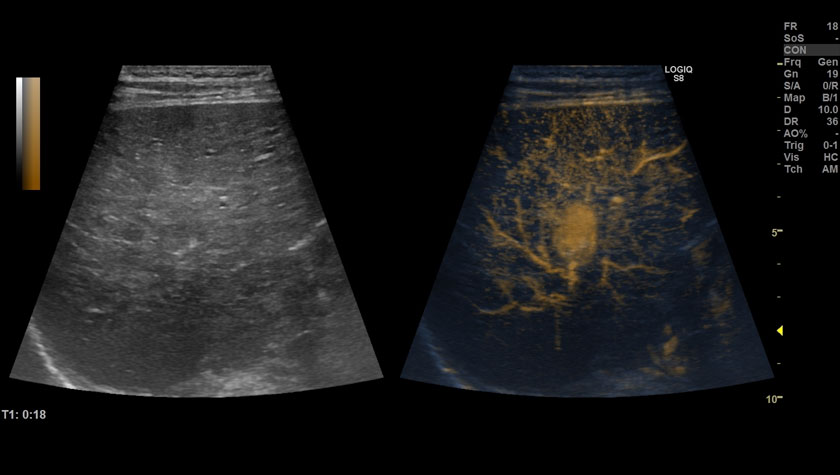

Ультразвуковая система LOGIQ S8 XDclear обеспечивает превосходное качество изображений: от рутинных случаев до технически сложных.

- Инновационные датчики XDclear и технологии – обеспечивают впечатляющую глубину проникновения и чувствительность даже у пациентов с избыточной массой тела. Система также обладает высокой разрешающей способностью и чувствительностью к кровотоку в мелких поверхностных и глубоколежащих сосудах.

- Режим B-flow – оценивает гемодинамику во всех типах сосудов: от крупных кровеносных сосудов, например, сонной артерии, до мелких сосудов паренхиматозных органов.

- B-Flow — Технология для высокоточной визуализации гемодинамики;

- Coded Contrast Imaging — Опция для исследования с контрастными веществами;

Сосудистая сеть шейного лимфоузла, УЗИ с контрастами (CEUS) + B-FLOW, датчик 9L-D

Печень, УЗИ с контрастами (CEUS), датчик 9L-D